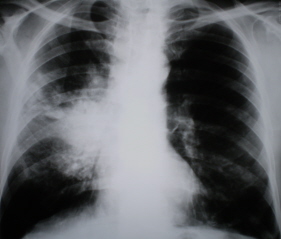

На линейных томограммах, произведенных в прямой проекции (иллюстрации 3, 4) участок сниженной прозрачности легочной ткани довольно однородной структуры. По верхнему контуру дифференцируются «мелкие линейные структуры», направленные каудально. Корень правого лёгкого раздельно не дифференцируется, на воне его отдельные очаговые уплотнения. На всем протяжении легочных полей дифференцируются отдельные очаговые тени малой и средней интенсивности, преимущественно в средних и нижних отделах легочных полей, хорошо определяющиеся в латеральных отделах.